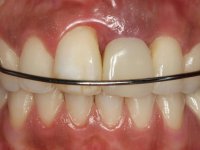

2) Tratamento ortodôntico com o objectivo de criar espaço entre as raízes e as coroas dos dentes 11 e 22,

As fotografias digitais simplificam a identificação das diferentes cores/shades do dente natural. A precisa recolha da cor/shade só se consegue se o paciente visitar o laboratório dentário. No caso presente, a necessidade da paciente vir ao laboratório foi discutida com o Dr. Couto Viana. A paciente percebeu a situação e, apesar da grande distância entre o Porto e Barcelona, deslocou-se ao laboratório dentário.